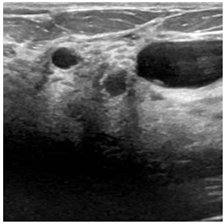

| Benign | Malignant | Normal | |

|---|---|---|---|

| BU images | ![]() | ![]() | ![]() |

| Number of images per class | 437 | 210 | 133 |